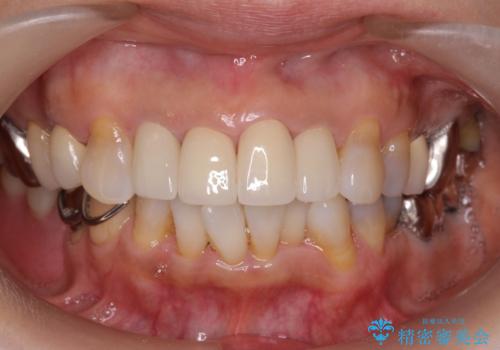

50代女性 前歯のつめものがとれた これを機に前歯をきれいにしたい

- 前歯の詰め物が頻繁に外れるとのことで来院。

これを機にセラミックでかぶせて、前歯の歯並びも良くしたいとのことでした。

両側の前歯もやり替えをすることで、前歯の前突感も無くしています。